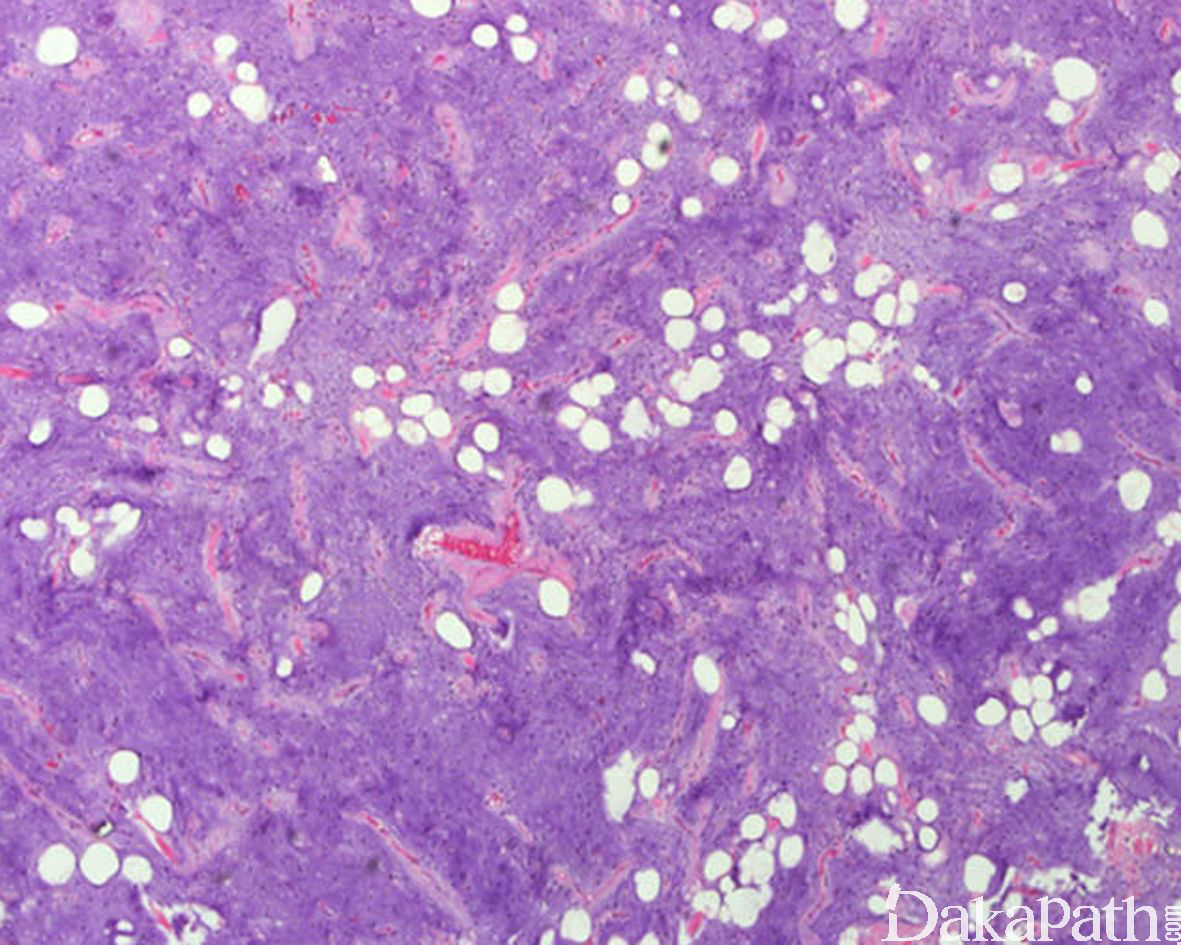

镜下由稀疏的短梭形或星状细胞混杂多少不等的成熟脂肪细胞组成;

间质呈广泛的黏液样或伴有局灶的绳索样胶原;

黏液样区内的梭形细胞或星芒状细胞核小而深染,胞质细长呈树突状;

纤维化区内梭形细胞核小,卵圆形,细胞之间为绳索样的胶原纤维,类似孤立性纤维性肿瘤;

可见丰富的小至中等大的血管及毛细血管,部分区域内可呈丛状,类似黏液性脂肪肉瘤;可见较多的肥大细胞浸润;